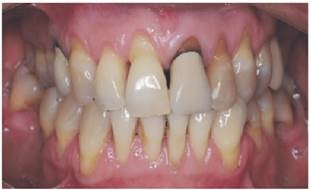

Fue seleccionada una paciente de género femenino, 53 años de edad, con presencia de múltiples recesiones Clase III de Miller y RT2 de Cairo, secuela de enfermedad periodontal y cepillado traumático (fig.1). Se modificó la técnica de cepillado y los elementos de higiene utilizados, además se eliminó el hábito tabáquico de 20 cigarrillos diarios por 25 años, y se le realizó tratamiento periodontal no quirúrgico. Luego, fue informada de las características del estudio dando su consentimiento informado.